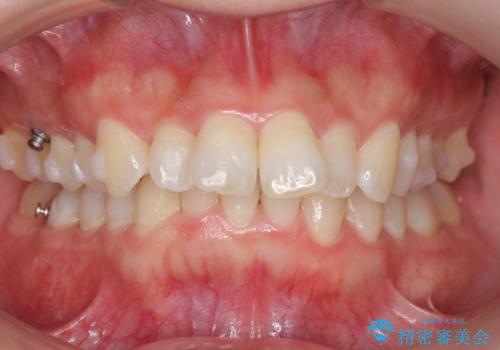

前歯をさげたい 歯を抜かずに マウスピース矯正で治したい

- 上の前歯が出ているとのことで来院。

歯を抜かずに、上の奥歯を後ろにさげつつ上の前歯を小さく少し削る処置を行い前歯の角度を修正しました。

右上下の奥歯もすれ違い咬合も、治療で改善しています。

下の前歯が生まれつき3本でしたので上下の正中は合わない仕上がりとなります。